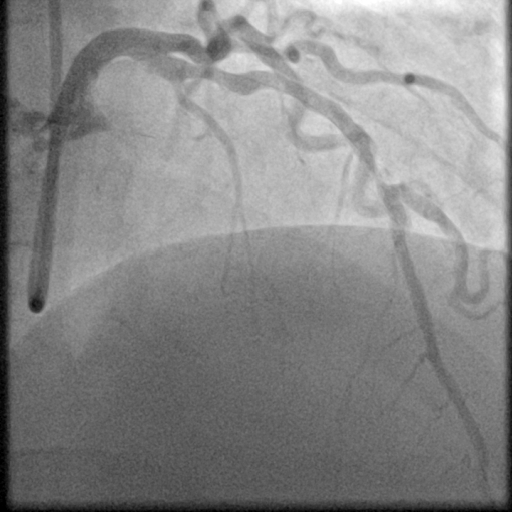

To further assess the detection performance, qualitative results for three test images are presented in Figure 2. The first column shows the original images with ground truth annotations. The second, third, and fourth columns depict detections from DINO-DETR, Grounding DINO, and YOLO, respectively.

(a) Original (b) DINO-DETR (c) Grounding DINO (d) YOLO

The qualitative comparison in Figure 2 reinforces the trends observed in the quantitative evaluation. DINO-DETR produced fewer detections, occasionally missing relevant stenotic regions, consistent with its conservative detection strategy aimed at minimizing false positives [6]. Grounding DINO, although capable of identifying more regions, sometimes resulted in cluttered predictions due to over-detections [7]. YOLO provided a reasonable trade-off by effectively capturing anatomical structures while maintaining relatively high confidence scores and clear visualizations [5].